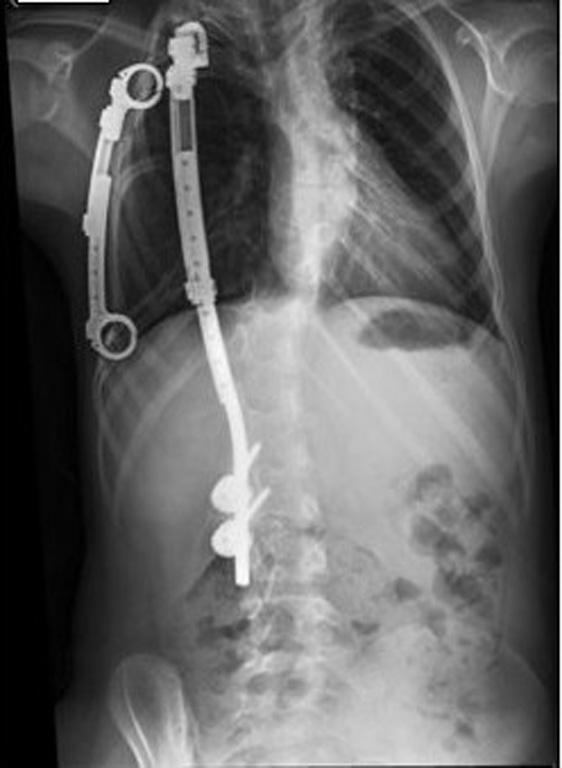

Grafilerle Skolyoz